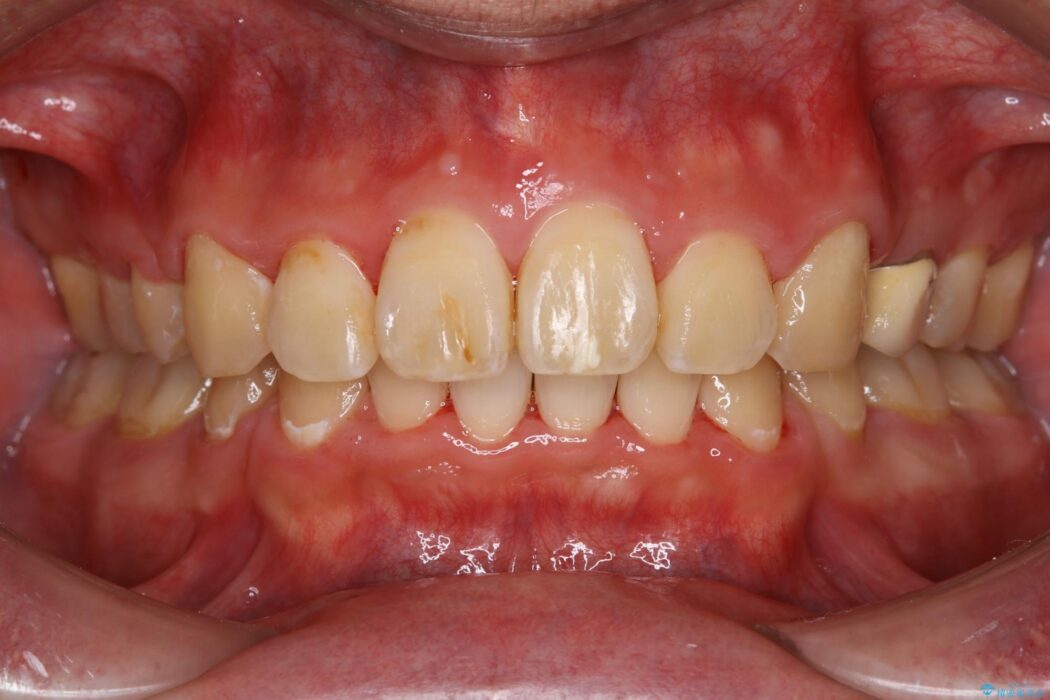

治療後について

ワイヤー矯正、マウスピース矯正、それぞれの特性、得意な治療がありますので、患者様の状態に合わせた治療器具の選択が大事となります。